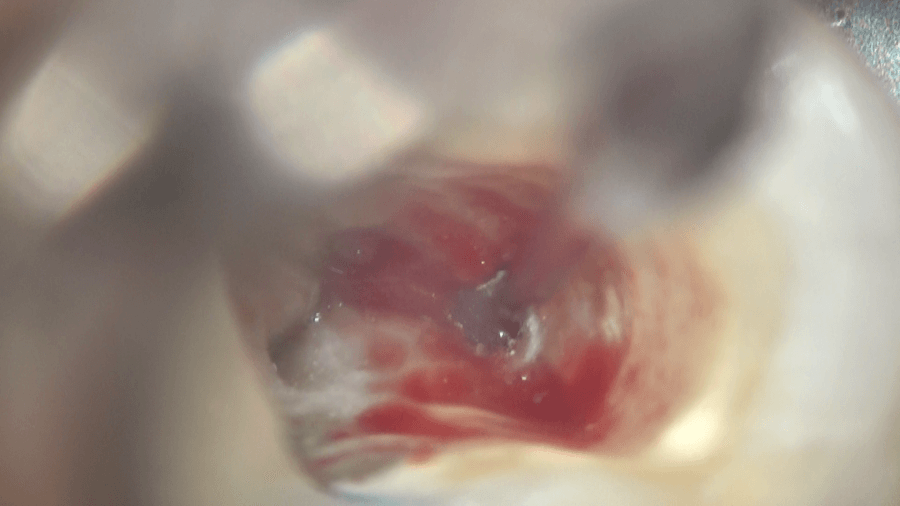

内部の軟組織である歯髄を次亜塩素酸ナトリウムで溶かします。

上部の歯髄を溶かすと、4つの根管の入り口が見えます。